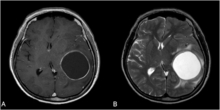

악성 뇌종양 교모세포종 환자 생존 예후인자가 규명됐다

- 2023-06-28 14:52

- 김민준 기자